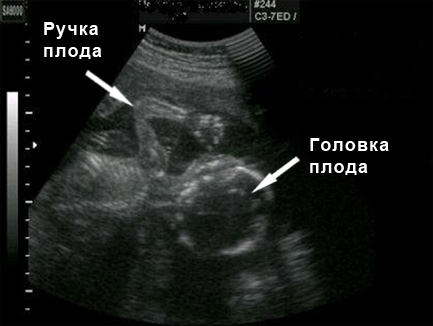

Фото УЗИ на 19 неделе беременности

В этот период основная задача ультразвукового исследования (УЗИ) заключается в проведении фетометрии, то есть измерении ключевых параметров плода. Это позволяет врачу оценить, правильно ли развивается ребенок. На 19-й неделе размер головы плода составляет 43 мм, объем живота – 120 мм, а длина бедренных костей – 30 мм. Кроме того, во время УЗИ с помощью допплерометрии исследуется маточно-плацентарный кровоток, что дает возможность определить, насколько хорошо плод получает кислород и есть ли какие-либо патологические изменения в плаценте.

Специалист также обращает внимание на носовую кость плода и воротниковую зону, что помогает выявить некоторые генетические нарушения и оценить работу сердца. Тщательно анализируются движения малыша, а также состояние околоплодных вод. В некоторых случаях, если ребенок расположен правильно, врач может определить его пол.

Кроме того, во время УЗИ врач внимательно осматривает плаценту, которая на этом сроке уже полностью сформирована. Ее толщина может достигать 2,5 см, а масса составляет около 450 г. Плацента обеспечивает малыша питательными веществами и кислородом, а также защищает его от негативных воздействий. Расположение плаценты влияет на силу ощущаемых толчков малыша. Если плацента прикреплена к задней стенке, движения будут ощущаться очень четко, в то время как при прикреплении к передней стенке шевеления могут быть менее выраженными. Если вы не чувствуете движений вовсе, это не всегда является поводом для беспокойства. Если результаты лабораторных анализов хорошие и УЗИ подтверждает нормальное развитие малыша, то переживать не стоит. Возможно, вы не ощущаете шевелений из-за индивидуальных особенностей или низкой активности ребенка. Также по статистике, женщины, ожидающие первого ребенка, могут начать ощущать движения только на 20-й неделе.